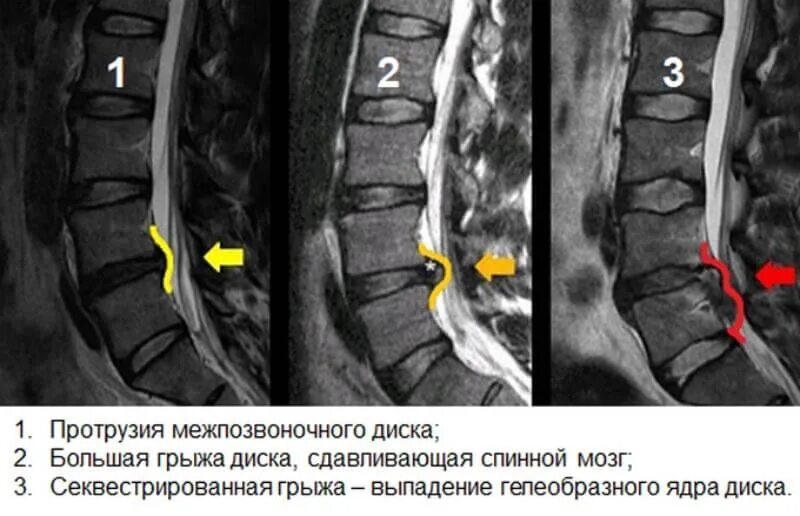

Лечение протрузии диска l5